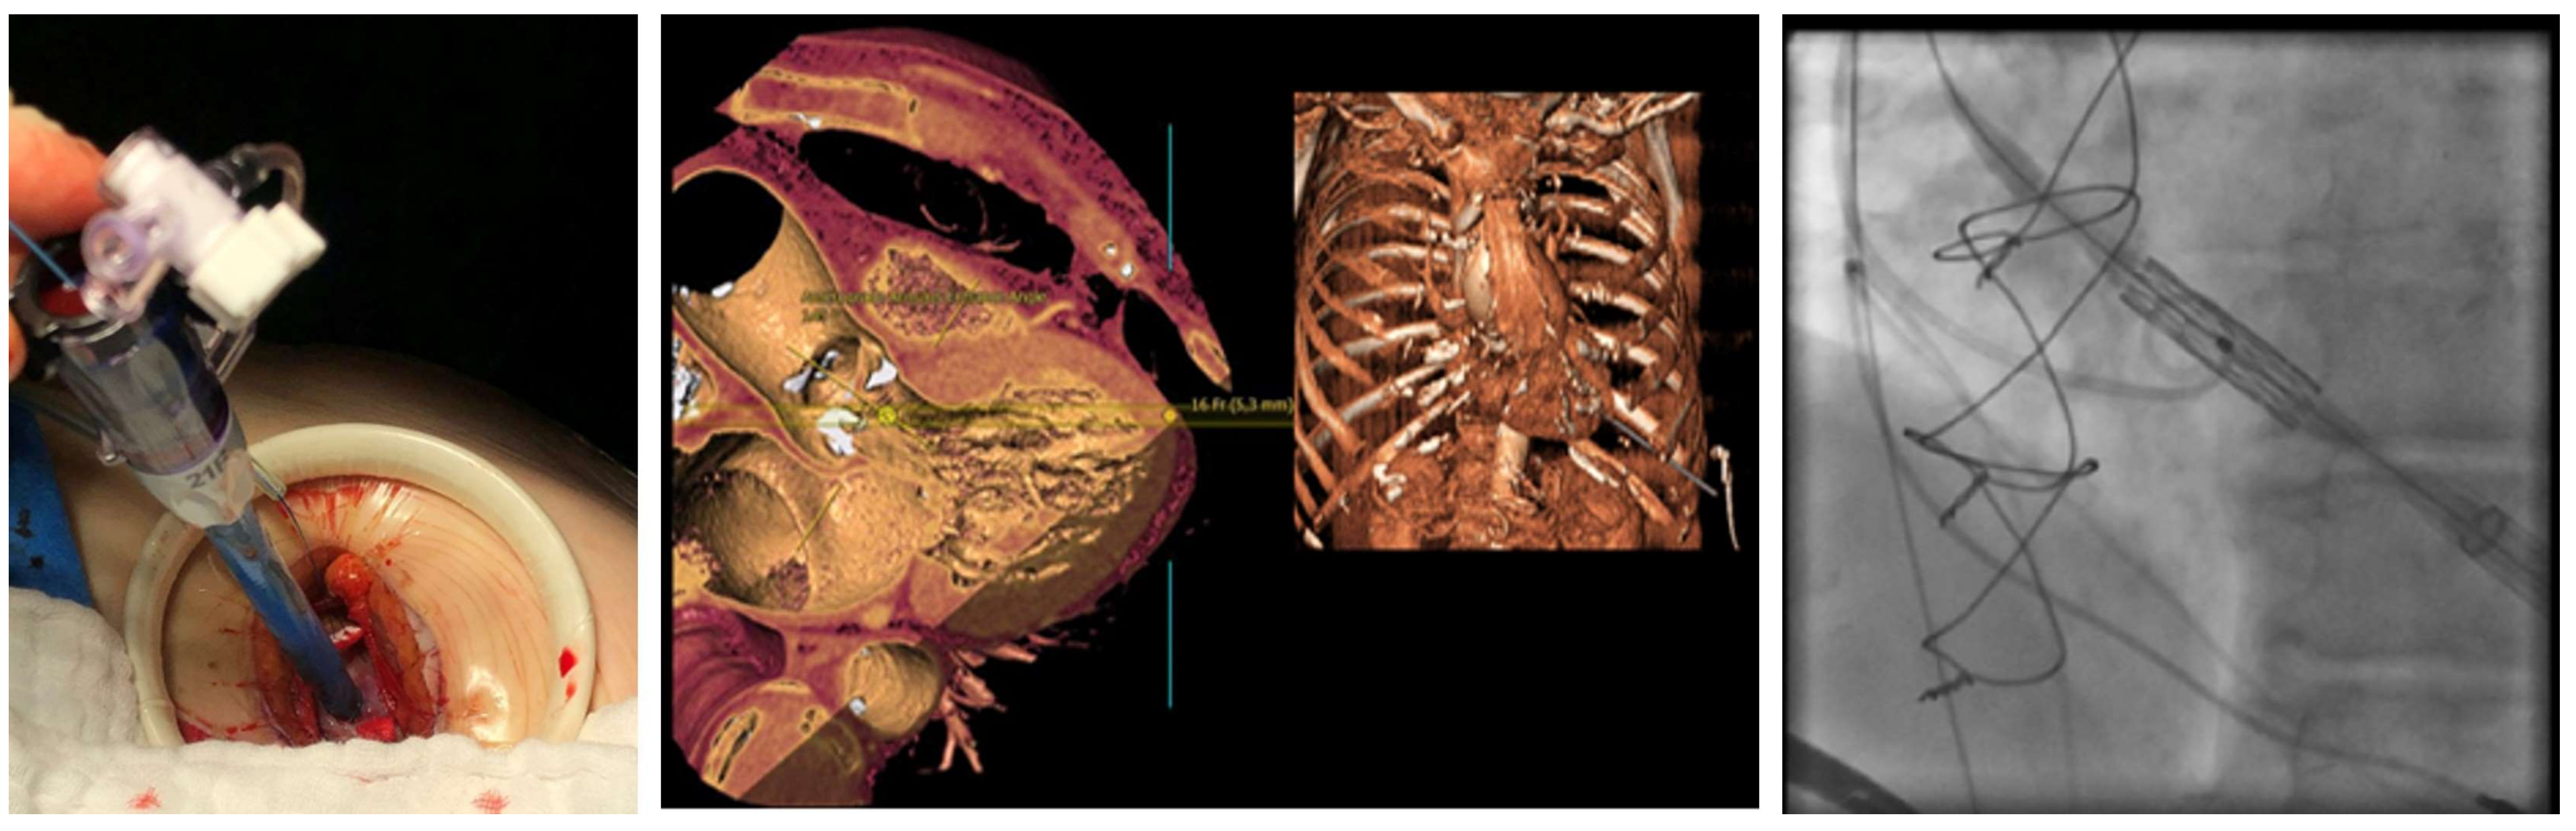

4.2. Procedural Characteristics